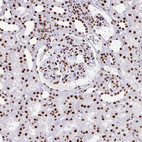

Immunohistochemical staining of human gastrointestinal, kidney, squamous epithelia and testis using Anti-EWSR1 antibody HPA062953 (A) shows similar protein distribution across tissues to independent antibody HPA051771 (B).